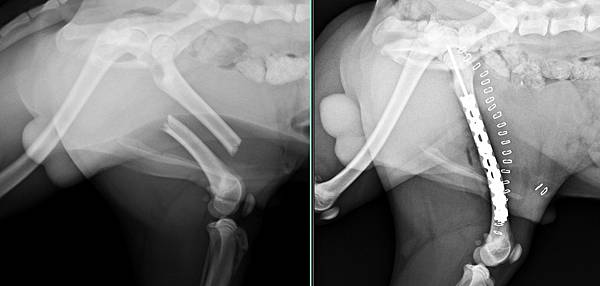

Sunny是一位很美的狐狸犬

有天受傷導致大腿骨折

骨頭刺出身體

我們也很順利的治療好開放性骨折